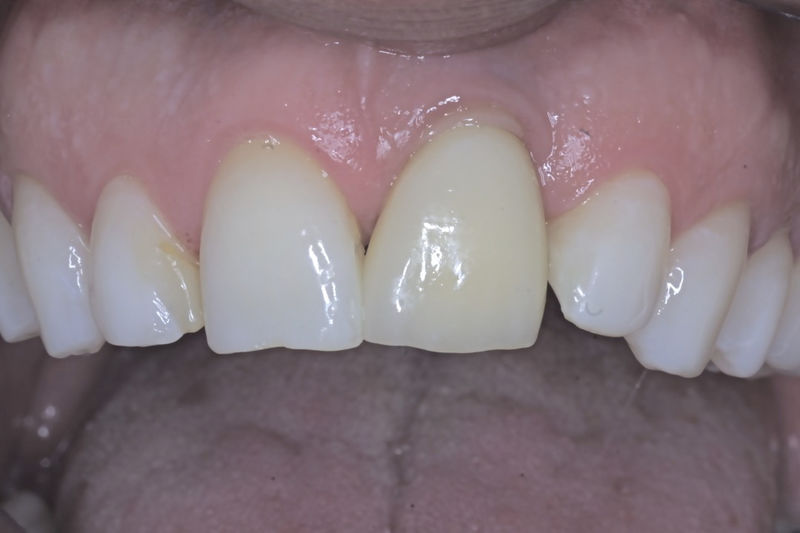

Amplia gama de tratamientos para mejorar la apariencia de la sonrisa, corrigiendo el color, la forma, el tamaño, la alineación y la posición de los dientes. Los procedimientos más comunes y solicitados incluyen el blanqueamiento dental, las carillas y coronas, así como las resinas.

Son restauraciones que cubren toda la cara frontal del diente, generalmente empleadas en el sector anterior y cuya finalidad es primariamente estética.

Restauraciones fabricadas en el laboratorio con materiales estéticos, los cuales cubren de manera total dientes anteriores y posteriores. Se utilizan primariamente para restaurar dientes con caries, fracturas y/o defectos amplios, así como soportes de puentes. Para poder enviar el caso al laboratorio se toman impresiones utilizando materiales de impresión o técnicas modernas digitales.